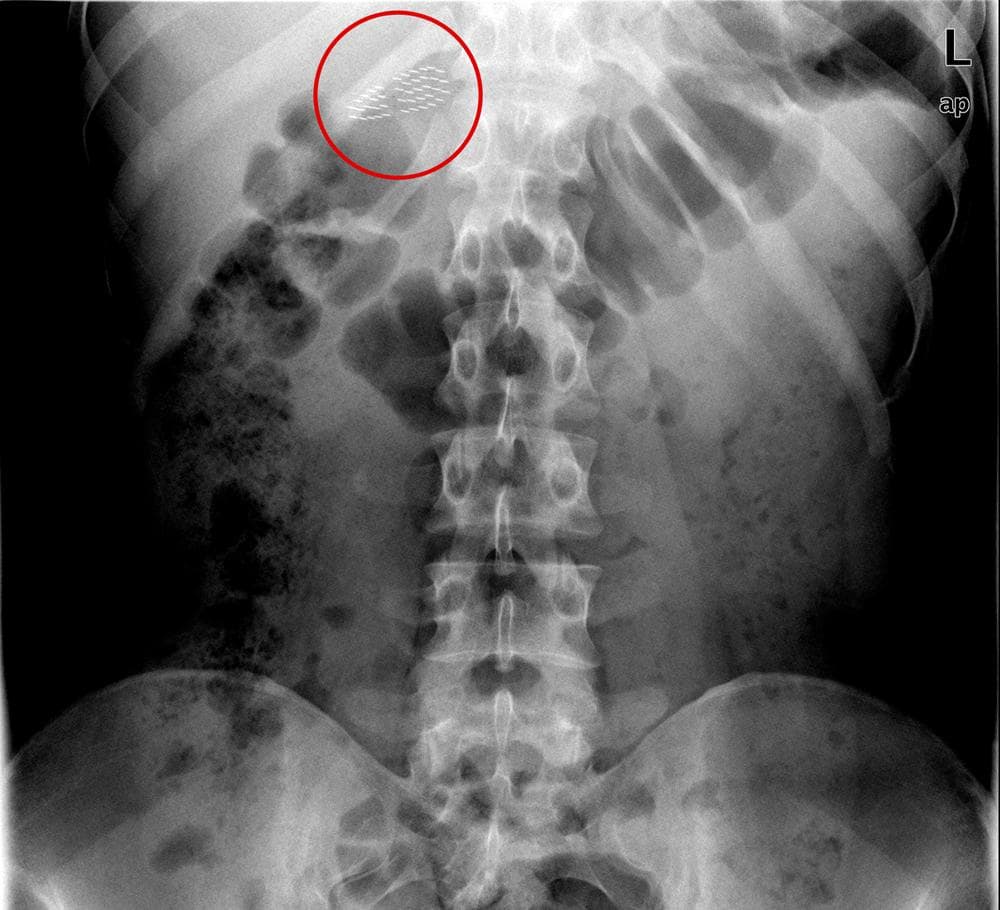

Swallowed toothbrush. Xray of the abdomen of a female patient who has Can You Swallow A Toothbrush instinctively, you swallow. a corresponding axial ct image in soft tissue window (b) reveals radiopaque bristles of stacked swallowed. in this study it was found that most cases of toothbrush ingestion were intentional (bulimia, induction of vomiting and mental. Though it’s rare, accidental swallowing of dental instruments happens — and can cause some serious complications. confronted. Can You Swallow A Toothbrush.